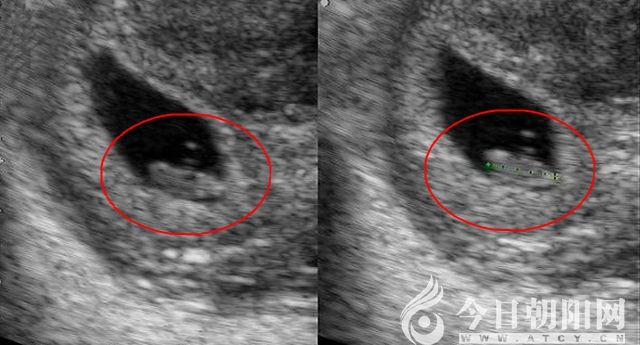

春節(jié)假期剛結束,朝陽市中心醫(yī)院生殖醫(yī)學中心又傳來好消息:2月12日,年前成功受孕的致遠夫婦(化名)來到醫(yī)院復查,按著醫(yī)生的指引,在超聲影像下看(聽)到了胎兒胎心穩(wěn)健而有力的波動。這預示著,一個鮮活的小生命正在母體中茁壯成長!

據(jù)了解,2018年11月,致遠夫婦在該院生殖醫(yī)學中心接受了“夫精宮腔內(nèi)人工授精”。2019年1月初,他們夫婦來院檢查時,“血清β—HCG”指標顯示:受孕成功!但由于天數(shù)少,還沒有辦法檢測到胎心。遵照醫(yī)囑,過了春節(jié)假期,夫妻倆趕忙來到醫(yī)院復查,在醫(yī)護人員表示祝賀的話語聲中體驗到了“種子發(fā)芽、健康成長”的喜悅。